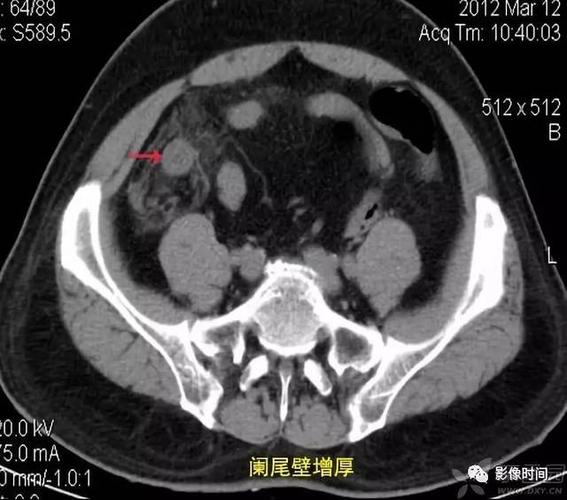

精品讲座急性阑尾炎的ct诊断

ppt急性阑尾炎的ct诊断

全面讲解正常阑尾和阑尾炎的ct表现

开课了急性阑尾炎的ct诊断及鉴别诊断

打基础 | 急性阑尾炎 ct 诊断

急性阑尾炎CT图片